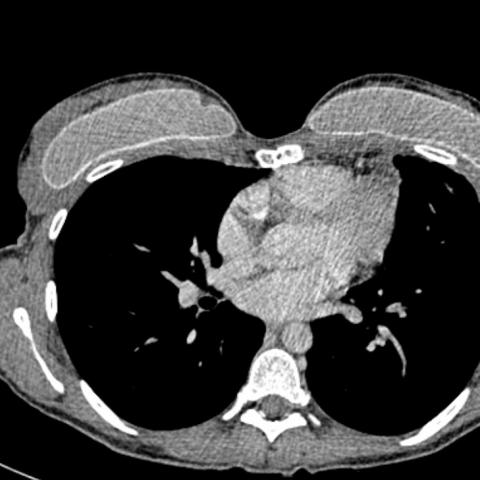

随后进行胸部对比增强CT(计算机断层扫描),结果显示非常大的团块占据左肺大部分,并且左上叶保留。团块由软组织组成,具有肉眼可见的脂肪灶,液性变薄的囊性区和多个钙化灶。CT进一步证实了纵隔移位的程度和左胸腔存在积液。纵隔淋巴结无明显肿大,无骨性病变,无肺扩张。组织学证实有大量成熟的肺内畸胎瘤。

图2 轴向CT显示,左肺内存在大量软组织团块,包括肉眼可见的脂肪、液性变薄的囊性区和多个钙化灶。少量胸腔积液,纵膈移位。